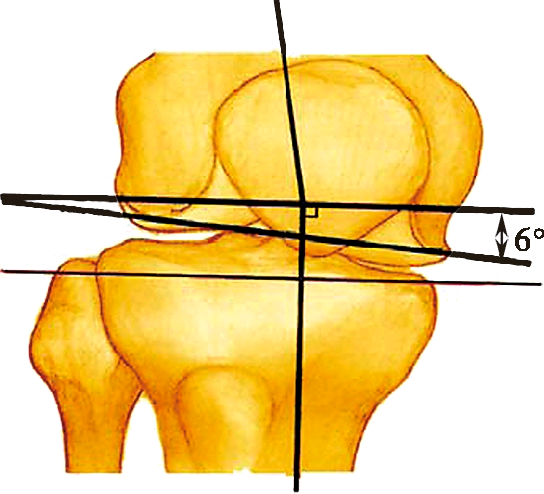

下肢力线也称下肢机械轴线,即站立位X线前后像股骨头中心与踝关节中心的连线。正常人体站立时,下肢机械轴通过膝关节中心,称为“中立”力学轴线。此时,股骨解剖轴与下肢力线有平均6°的外翻角;胫骨解剖轴与机械力线重合。在病理情况下,由于膝关节内翻或外翻,下肢的机械轴将会偏离膝关节的中心。膝内翻时下肢机械轴位于膝关节中心内侧,膝外翻时下肢机械轴位于膝关节中心外侧。膝关节置换术后,股骨假体通常有5°~7°的外翻,现代胫骨假体的设计在冠状面上通常与机械轴垂直,这对于重建“中立”力学轴线是至关重要的

股骨解剖轴是股骨大转子尖与股骨髁间窝中点的连线。股骨解剖轴纵贯股骨髓腔中心。股骨解剖轴与机械轴的夹角平均约6°,临床上称其为“远端股骨角”。

胫股角(femoraltibial angle,FTA)是股骨解剖轴线与胫骨解剖轴线在膝关节中心相交形成的向外侧的夹角。此夹角平均为174°。